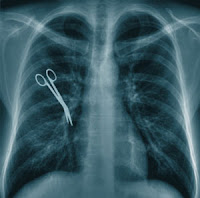

It’s their fault, right? Yes, their fault you have cancer, are de-conditioned and ripe for disk herniation, or have complications with your routine surgery. They failed to find the problem, test well enough, or prescribe the proper treatment. Right?

Yes that’s how it happens. And it’s why medical malpractice is through the roof. It’s why doctors order an inordinate amount of tests, whether you really need them or not—to protect their arses! It’s why medical costs are astronomical (if you are still living by the illusion that medical costs are out of control because people don’t have federally funded health insurance, then there may be no hope for you…ever) and will continue to grow until something changes.